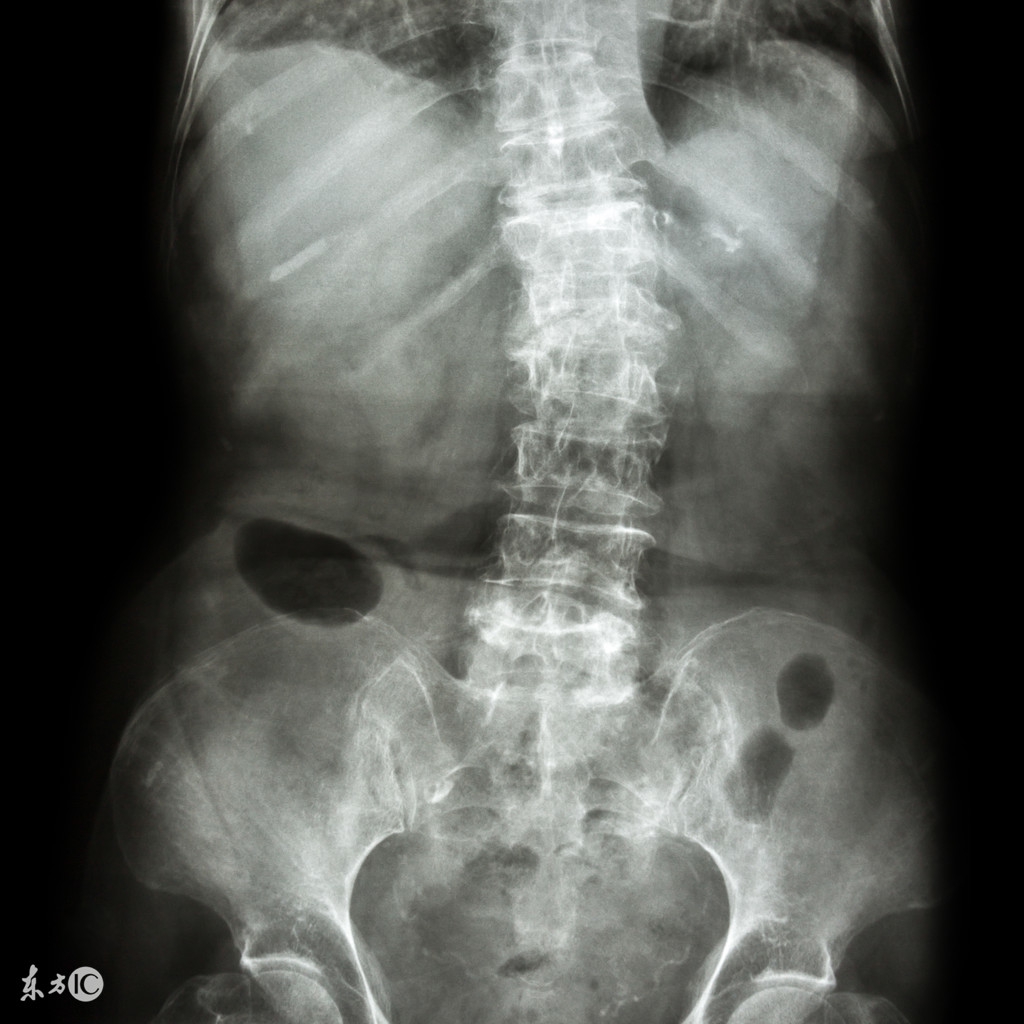

自古以来“民以食为天”,如果食补亦能治病,方是良策。强直性脊柱炎患者采取食补同样能较好较快恢复身体。对于患者而言,强直性脊柱炎患者吃什么好呢?在患病期间以及术后饮食应注意什么?请看下面相关的饮食指南。

强直性脊柱炎患者吃什么好?